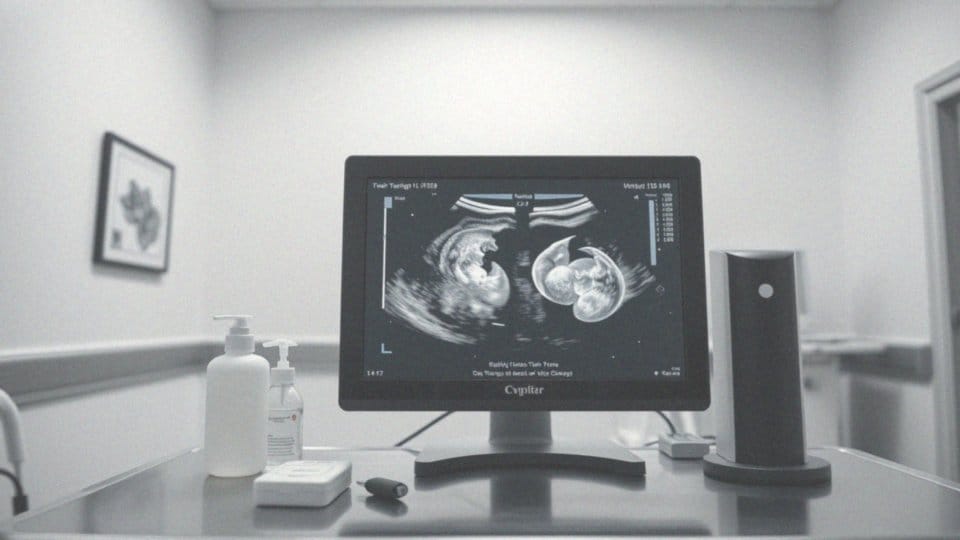

Bliźnięta MoMo, znane również jako jednoowodniowe, to niezwykły typ jednojajowych bliźniaków. Dzieląc zarówno łożysko, jak i woreczek owodniowy, niosą ze sobą istotne zagrożenia zdrowotne. W przypadku ciąży MoMo ryzyko komplikacji wzrasta. Dzieci w takiej ciąży są bardziej narażone na tzw. „sudden twin demise”, co oznacza, że jeden z płodów może zaprzestać rozwoju, a to może mieć poważne konsekwencje dla drugiego maluszka. Dodatkowymi zagrożeniami są:

Interesująca statystyka sugeruje, że ciąża z bliźniętami MoMo zdarza się w około 1 na 10 000 ciąż, co pokazuje, jak rzadki jest to przypadek. Ze względu na podwyższone ryzyko, takie ciąże wymagają szczególnej opieki medycznej i często są monitorowane za pomocą zaawansowanych technik obrazowania. Poprzez odpowiednią interwencję medyczną, istnieje szansa na zdrowe narodziny dzieci. Jednak bliskość obu płodów w jednym worku owodniowym czyni ciążę MoMo wyjątkowym wyzwaniem, zarówno dla matki, jak i zespołu medycznego. Warto zauważyć, że bliźnięta MoMo klasyfikowane są jako jednokosmówkowe, co oznacza, że dzielą kosmówkę, lecz mogą mieć różne stany zdrowia. Z tych powodów, ciążę MoMo uznawana jest za szczególnie rzadki przypadek w medycynie, ze względu na jej unikalne i wymagające cechy.

Bliźnięta MoMo to niezwykle rzadki typ ciąży mnogiej, który wyróżnia się jednoczesnym dzieleniem łożyska oraz worka owodniowego. Tego rodzaju ciążę określamy mianem jednokosmówkowej-jednoowodniowej. Ciekawe jest to, że ciążę jednokosmówkowe zdarzają się zaledwie w około 1% przypadków u bliźniaków, a bliźnięta MoMo stanowią tylko 0,1% tych sytuacji.

Ciężę MoMo to zjawisko niezwykle rzadkie, występujące w przybliżeniu w jednym na 35 000 przypadków, co odpowiada tylko 1% wszystkich ciąż bliźniaczych. W porównaniu z innymi rodzajami ciąż, właśnie te charakteryzują się wyższą umieralnością płodów. Szacuje się, że nawet połowa takich ciąż kończy się martwym porodem jednego albo obydwu bliźniaków. Gdy jednak rodzą się zdrowe dzieci, ich wskaźniki przeżycia wynoszą od 60 do 70%. Niestety, ciąże MoMo niosą ze sobą większe ryzyko powikłań, takich jak zaciśnięcia pępowiny czy interakcje między płodami. Nowo narodzone dzieci często wymagają intensywnej opieki neonatologicznej, a ich stan zdrowia może wymagać monitorowania także po porodzie.

Bliźnięta MoMo to fenomen, który zdarza się niezwykle rzadko, ponieważ ich narodziny przypadają na zaledwie 1 na 35 000 porodów. Oznacza to, że stanowią jedynie około 1% wszystkich ciąż bliźniaczych, co czyni je szczególnym przypadkiem w medycynie. Narodziny bliźniaków MoMo wiążą się z wyższym ryzykiem komplikacji, w tym z tragicznie wysoką umieralnością płodów, która może sięgać nawet 50%.